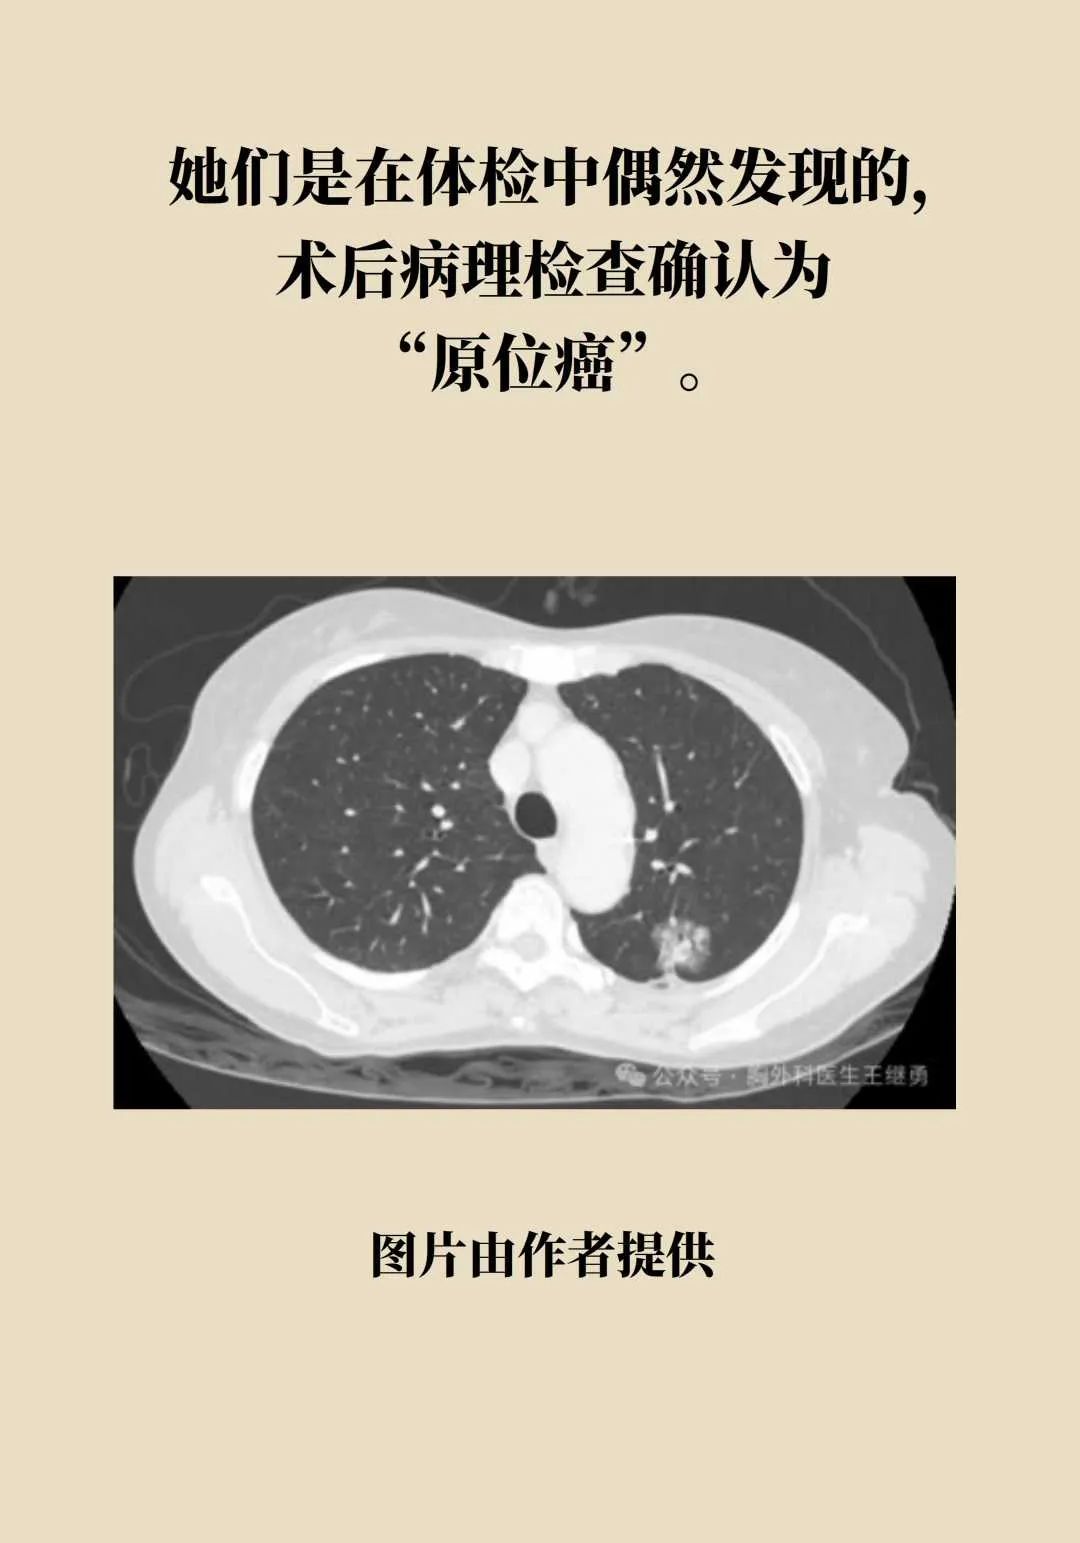

4台肺癌手术,2名“90后”患者,这届年轻人的肺怎么了?

原标题:《4台肺癌手术,2名90后患者!这届年轻人的肺怎么了?》